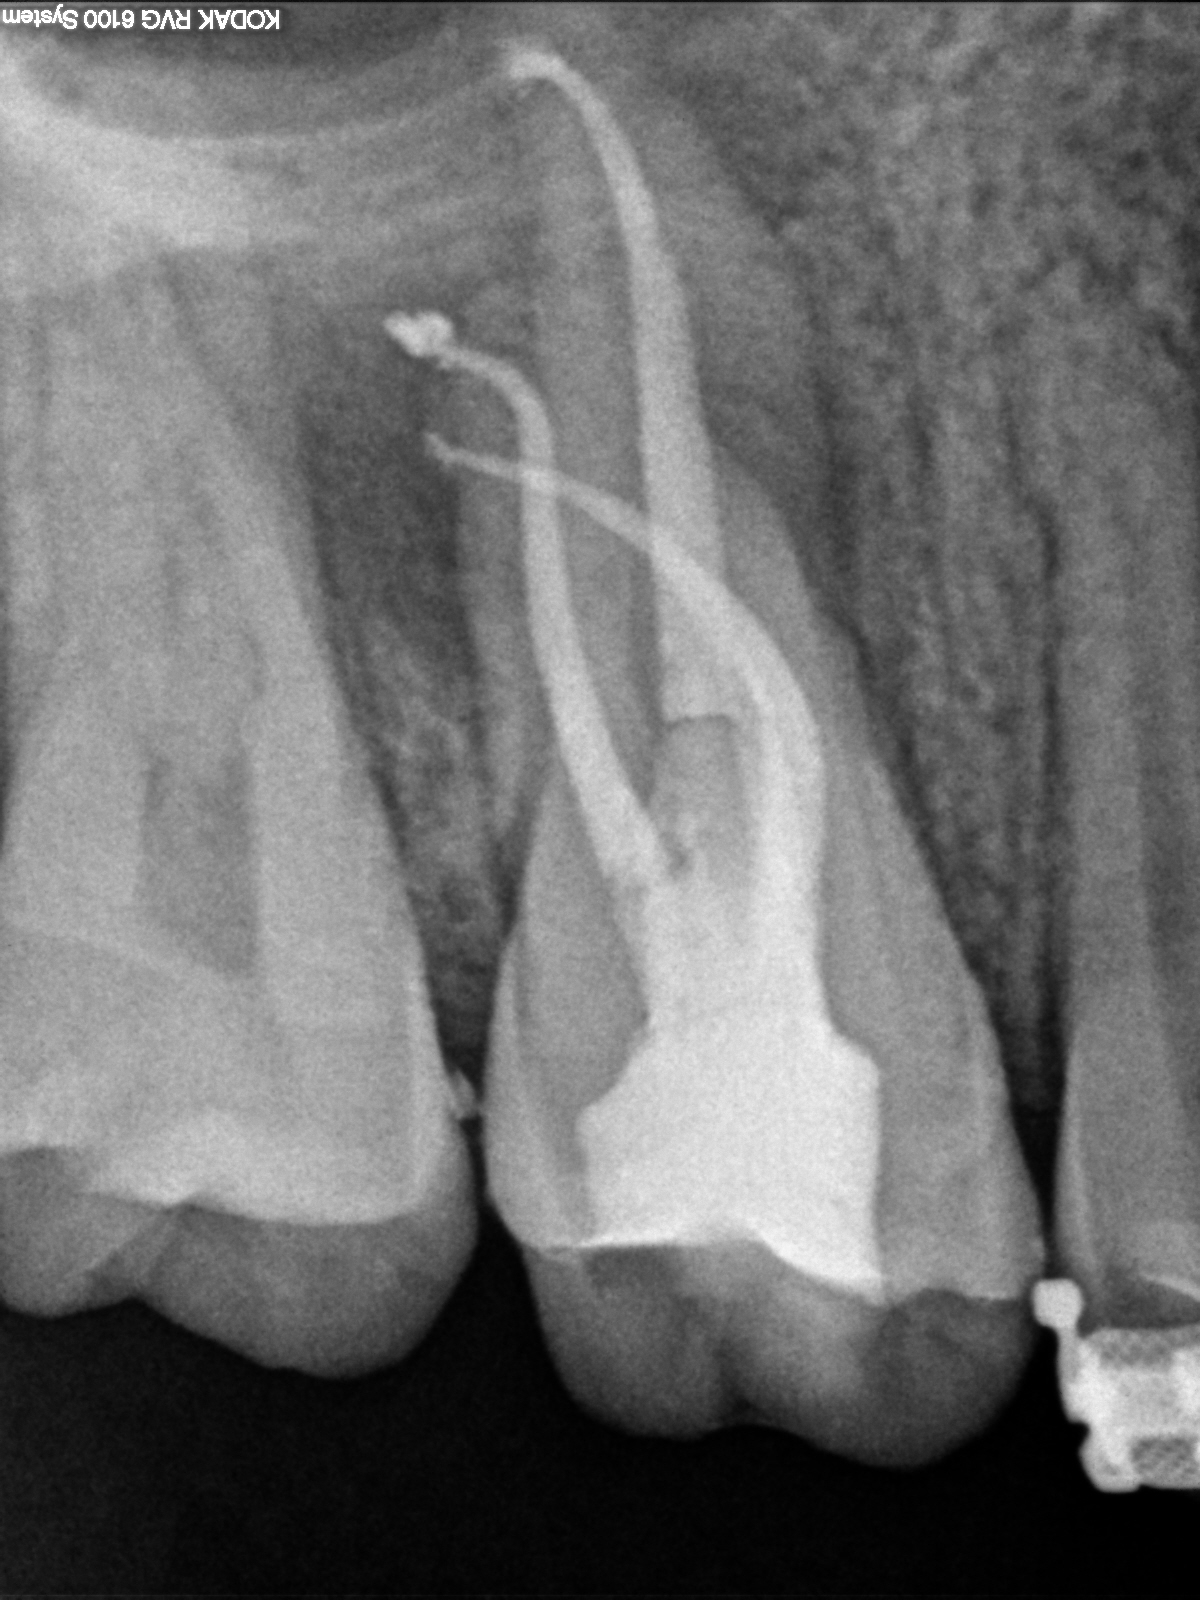

4) post-op

post-op